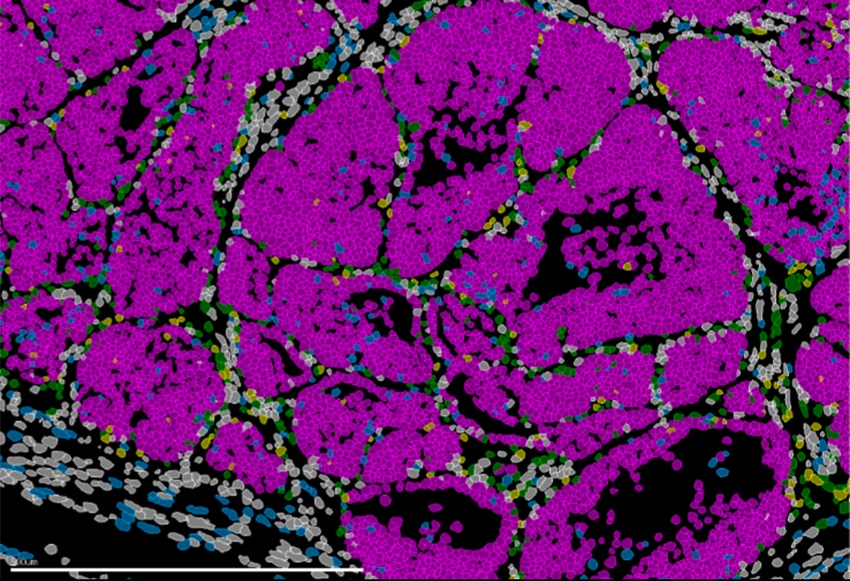

Todos los participantes fueron evaluados por un panel de expertos para confirmar sus diagnósticos. Se les tomaron pequeñas biopsias de piel (3 mm) en tres lugares: cuello, rodilla y tobillo. Posteriormente, se analizaron para detectar la presencia de P-SYN. Los resultados se publicaron en la Revista de la Asociación Médica Americana el 20 de marzo de 2024.

El equipo descubrió que las biopsias cutáneas permitían detectar una alta proporción de participantes con sinucleinopatías. Se detectó P-SYN en el 93 % de los pacientes con enfermedad de Parkinson clínicamente confirmada (89 de 96 personas). Las biopsias fueron aún más eficaces para las demás afecciones, identificando al 98 % de los pacientes con atrofia multisistémica (54 de 55) y al 96 % de los pacientes con demencia por cuerpos de Lewy (48 de 50). Además, las biopsias identificaron a los 22 participantes con diagnóstico clínico de insuficiencia autonómica pura. En cambio, se detectó P-SYN solo en el 3 % de los participantes de control.